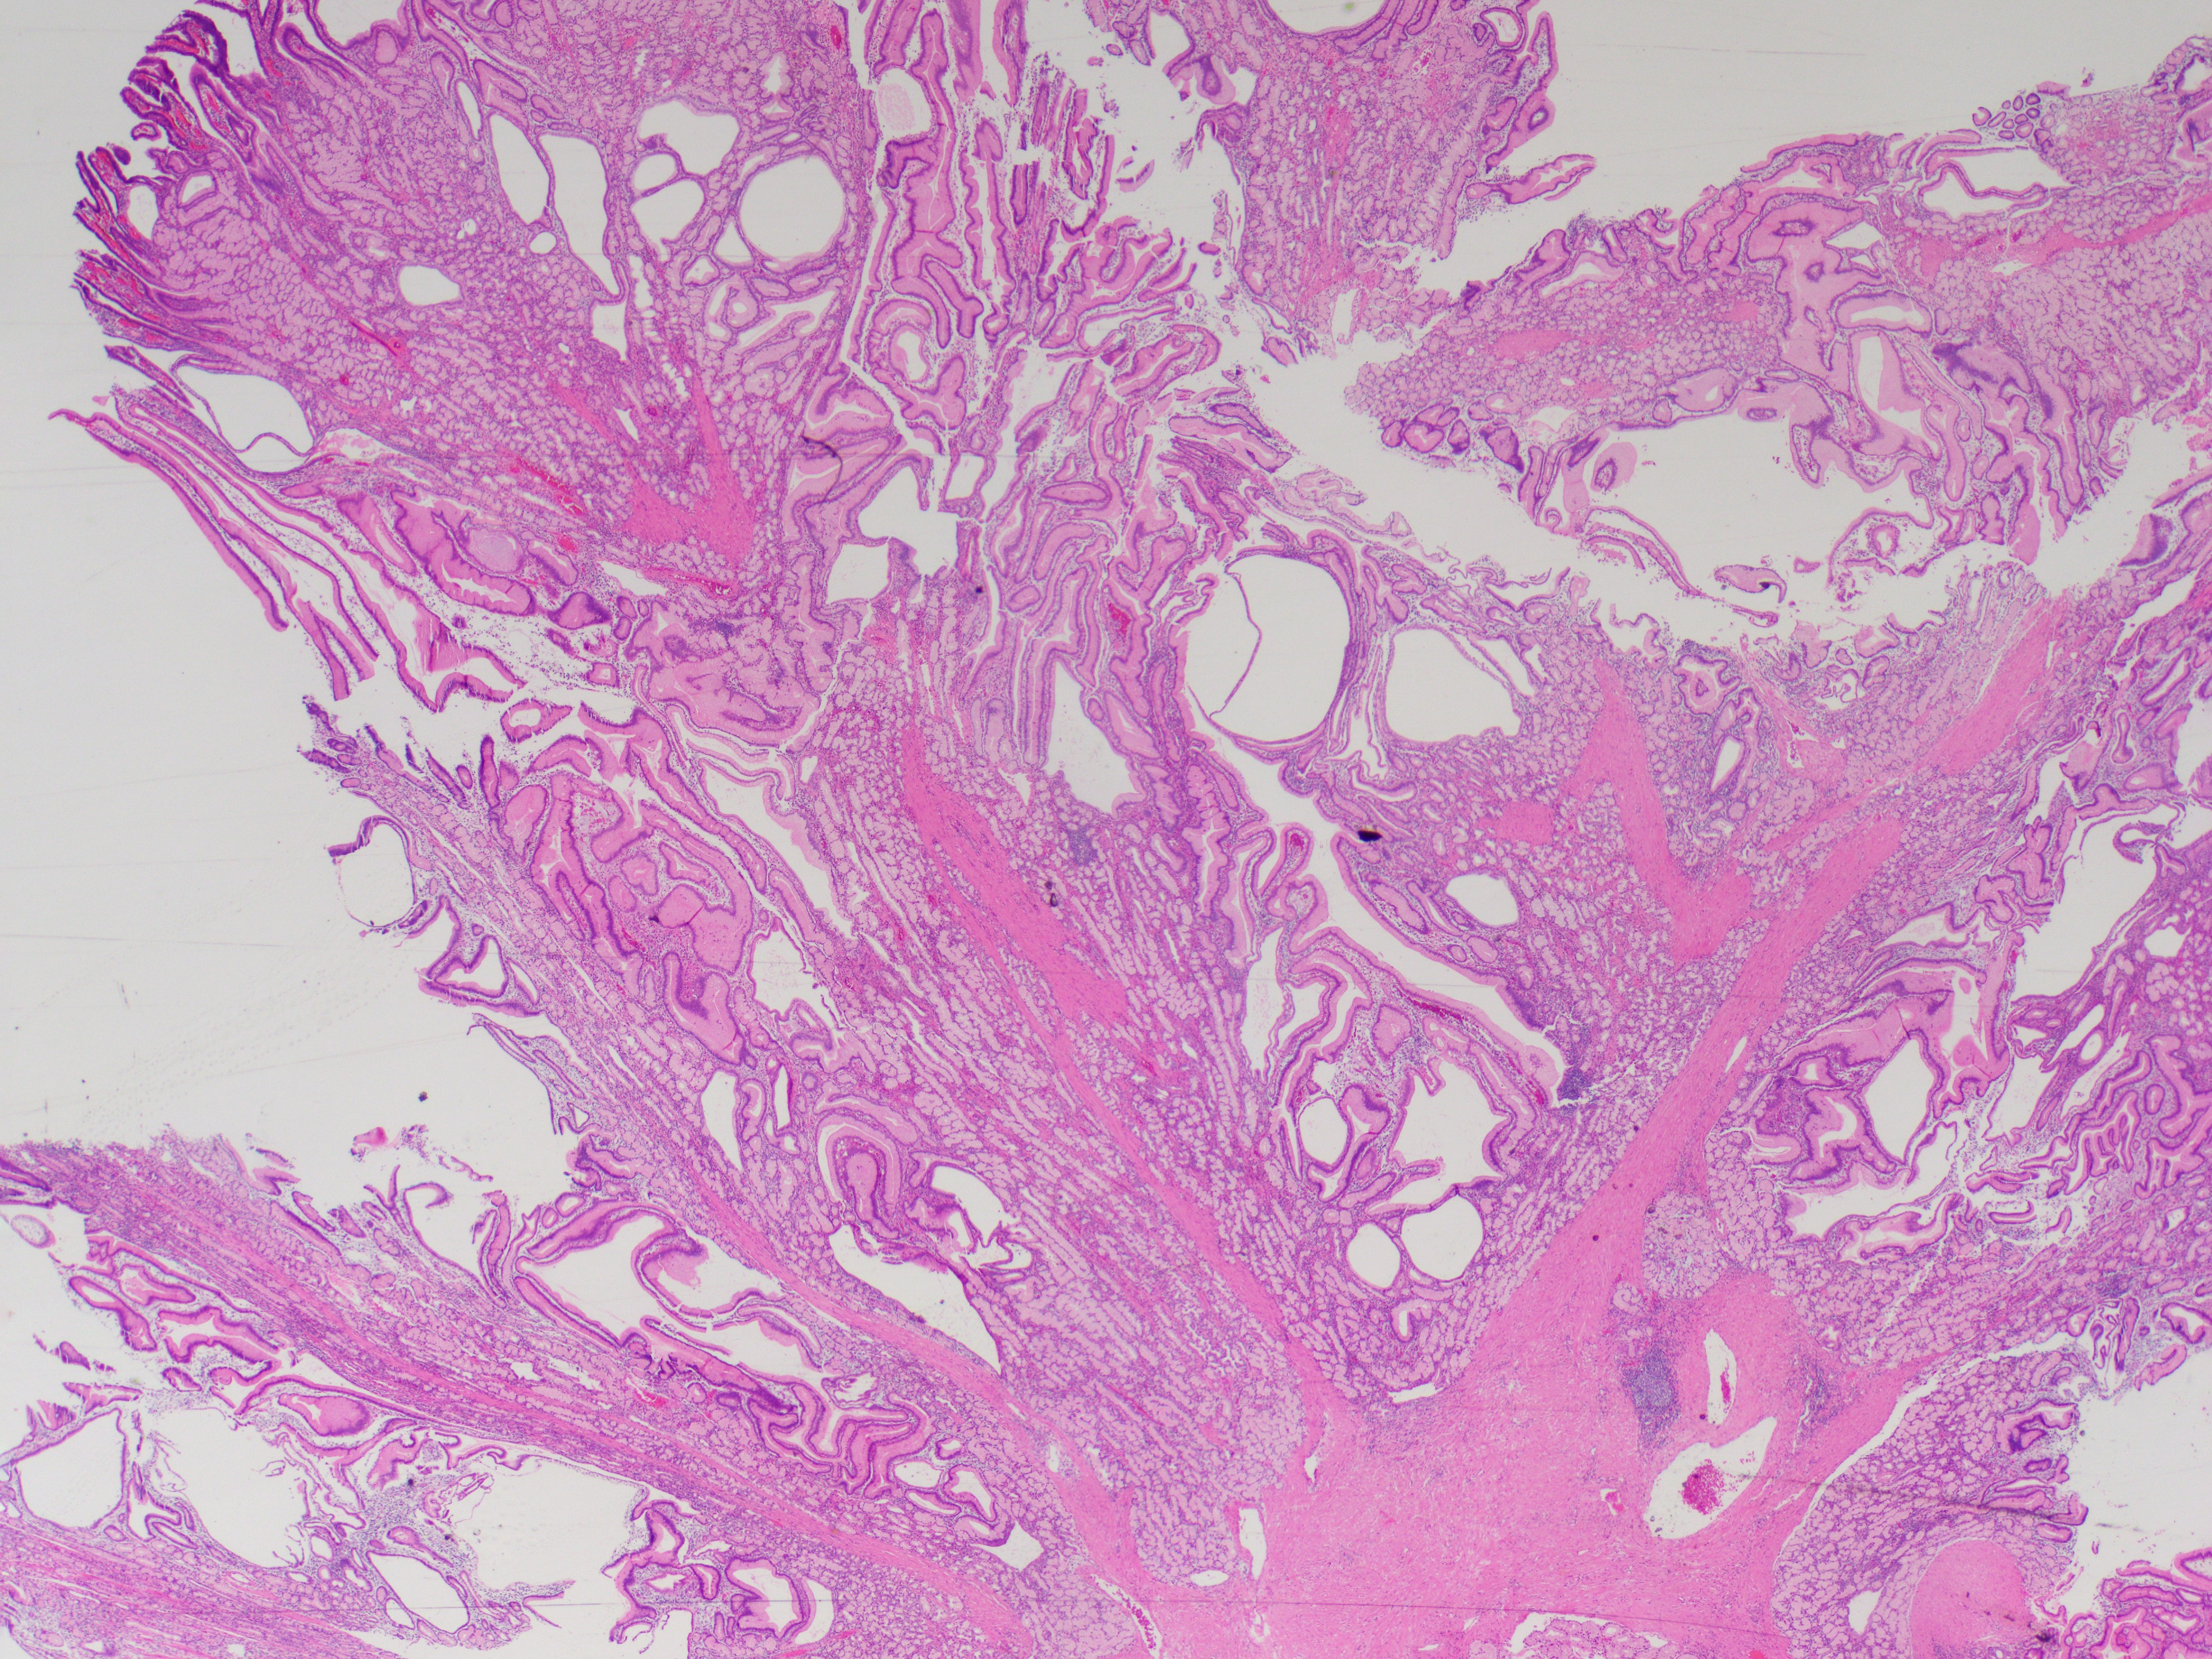

A male patient in his mid-thirties with a personal and family history of polyps underwent duodenal polypectomy.